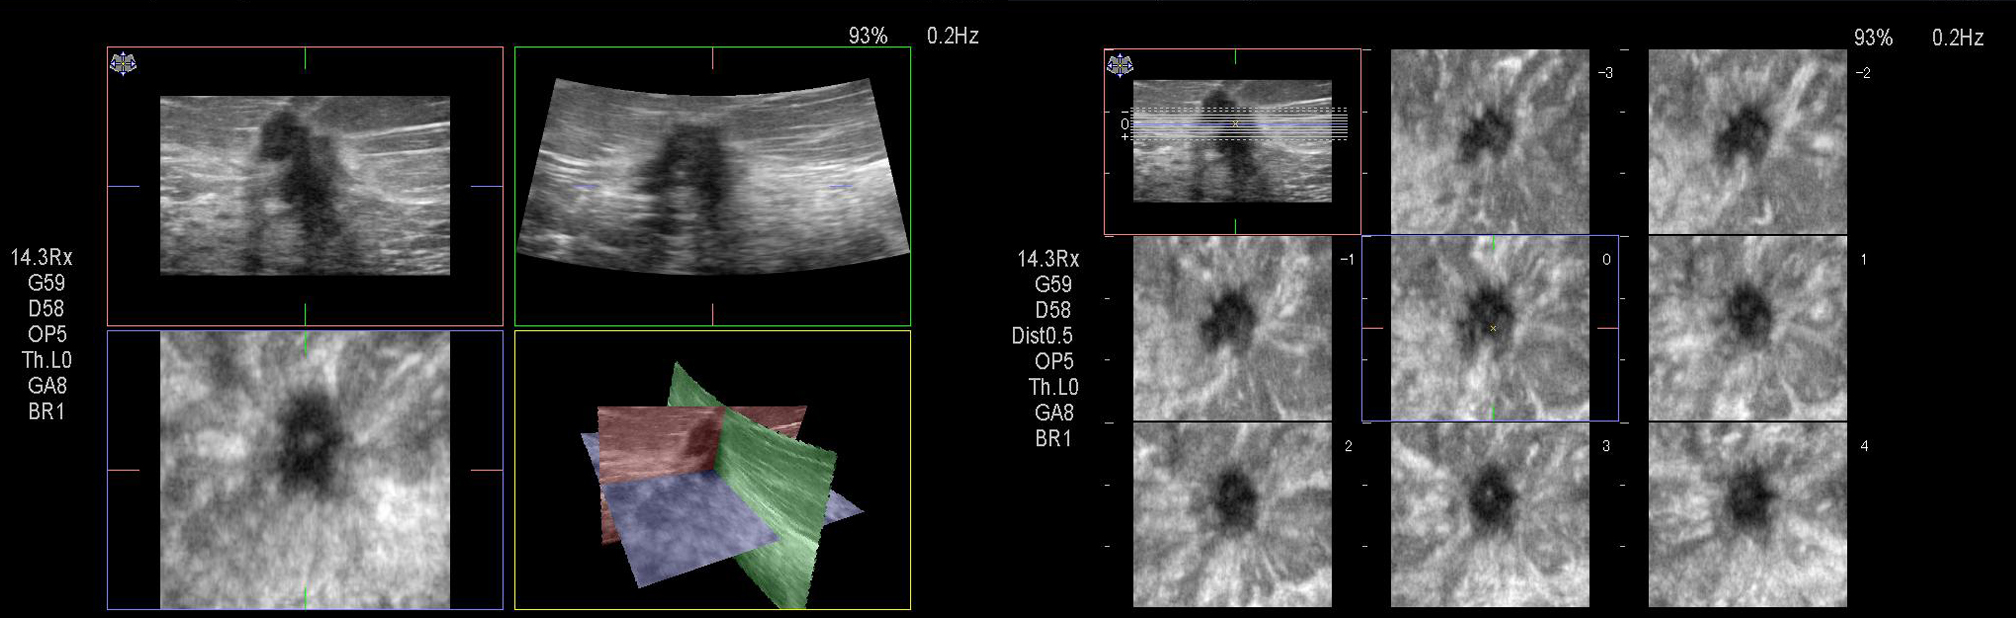

auffällige 3D-Mammasonographie und Multi-Slice-Darstellung